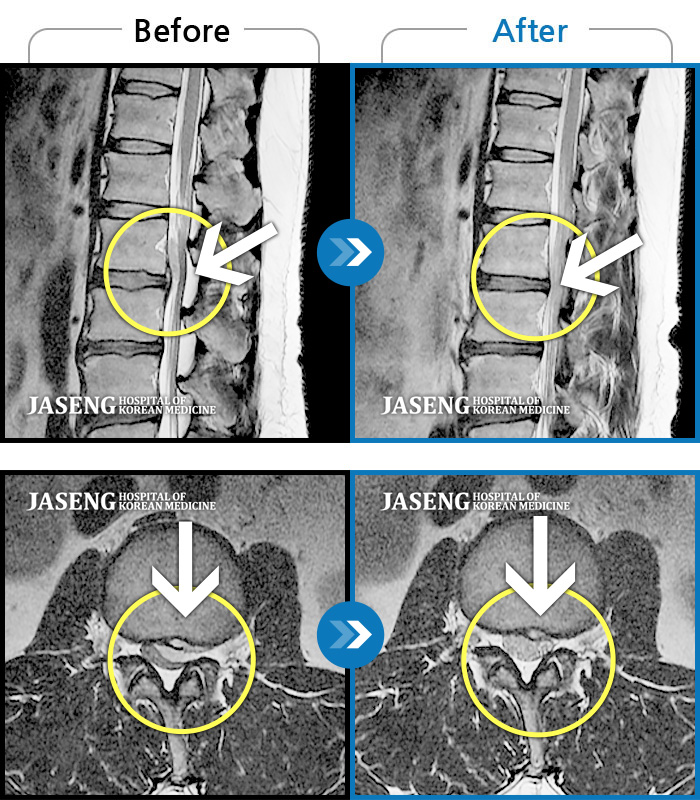

MRI 치료사례

허리통증 및 우측 하지 방사통, 풋드랍 진행